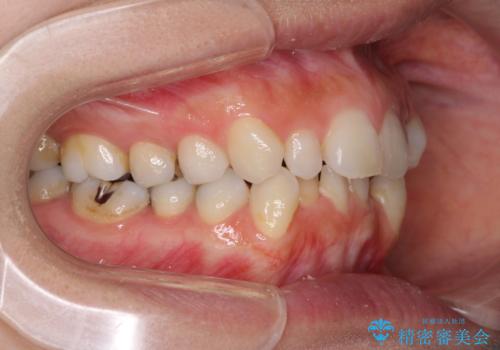

- 前歯のデコボコと矮小歯、更には痛みを感じる奥歯のむし歯を気にして来院された患者様です。

奥歯には根管治療が必要な歯があり、上顎側切歯は左右ともに矮小歯でした。

上下前歯のデコボコはワイヤーでもインビザラインでも対応可能でしたが、補綴治療が多く必要となることから、インビザラインでの矯正治療を行いながら、並行して補綴治療を行うこととしました。

まずは根管治療を行った上で矯正治療用の仮歯を装着し、矯正治療後半に補綴治療を並行して行うこととしました。